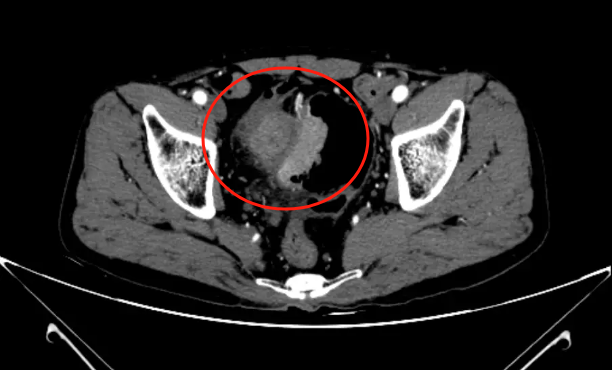

通过进一步检查发现,冯先生肠道内 多发占位,考虑 肿瘤性病变。其中升结肠见环腔肿物基本占据整个肠腔,直乙交界处巨大肿物侵犯膀胱。

直肠肿瘤